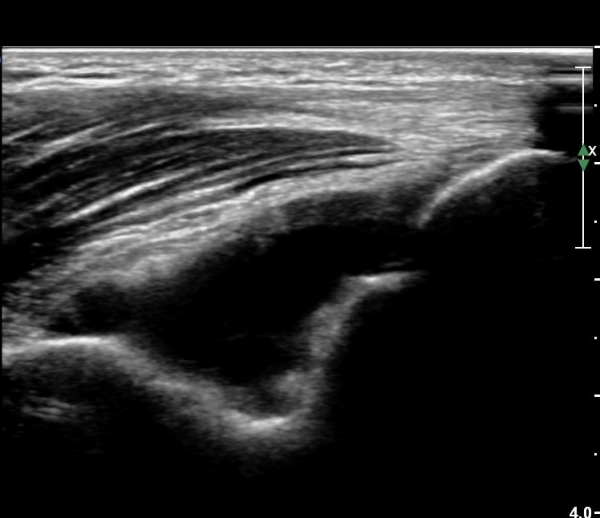

ÃÊÀ½ÆÄ °Ë»ç

ÆÈ²ÞÄ¡ ¾ÕÂÊ ¼ÒµÎ Á¾´Ü¸é°Ë»ç¿Í Ⱦ´Ü